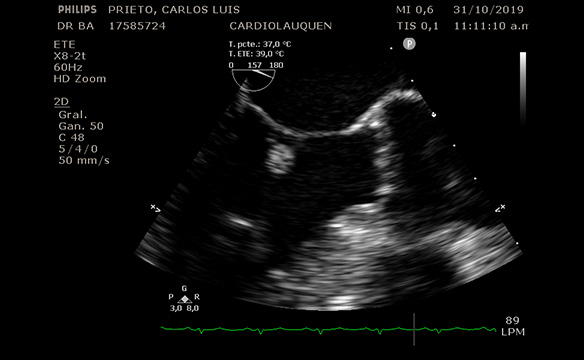

Paciente de 56 años de edad, sin antecedentes patológicos que consulta en nuestro centro a la Dra. Barr por episodio sincopal mientras se encontraba en baile.

TA : 120-80 mm hg. No soplos. Pulsos y pulmones normales. ECG normal. Afebril.

ECO DOPPLER y ETE, equipo Phillips 3D (Dra. Barr y Tec. En imágenes Lucia Vacas): imagen en Valva Mitral redondeada de 0.8 mm, muy móvil, sin compromiso de ecoestructura Mitral luego fue evaluado en consulta con Dr. Avegliano, confirmando la sospecha de que por las características de dicha masa puede corresponder a Fibroelastoma Papilifero. Dada la alta incidencia de embolia, se envía a Cirugía Cardiovascular.

Fecha: Nov. 2019

Aparato: Eco Doppler/ETE

Autor: Dra. Barr